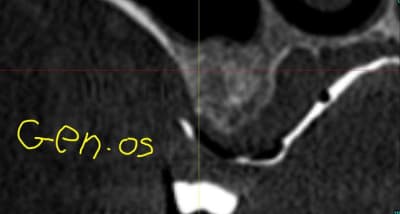

à gauche :GEN-OS

- pas de particules

- ressemble d'avantage à de l'os

- pas de sensation de bouillie

- semble plus homogène

- résorbable

- pas d'effet barrière contre la pneumatisation du sinus

- taux de résorption inconnu